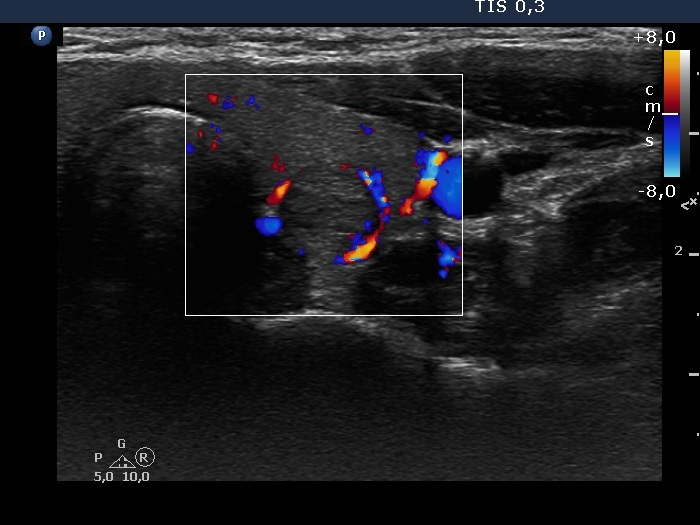

Consecutive patients with the final diagnosis of Hashimoto's thyroiditis - case 27 (389) (ultrasonographic picture 6)

Left lobe, transverse scan, color Doppler mode. The lesion has perinodular blood flow.